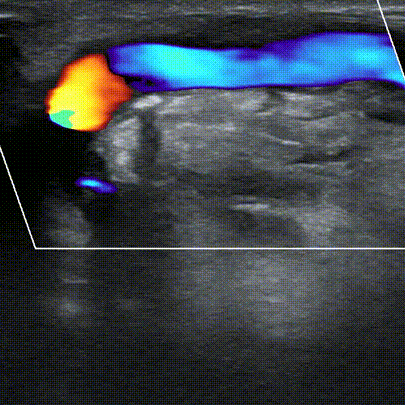

吻合口血流信号丰富。

术后肱动脉血流量900ml/min